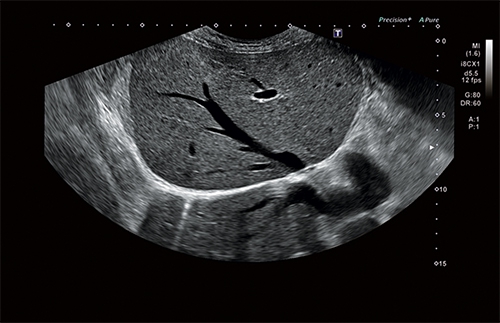

Автоматический расчет воротникового пространства

Специальная функция поможет вам провести более точное исследование накопления жидкости в воротниковом пространстве плода при текущей беременности матери. Это позволит специалистам минимизировать риски врачебной ошибки при выявлении различных заболеваний, связанных с хромосомными отклонениями.

Автоматическое измерение основных параметров биометрии плода в акушерстве

Удобная в использовании функция данного УЗ аппарата позволит вам с большей эффективностью определить и выявить возможные отклонения при наблюдении за развитием плода во время беременности. Опция автоматического расчета не только снижает риск возможной врачебной ошибки, но и помогает ускорить проводимое исследование.